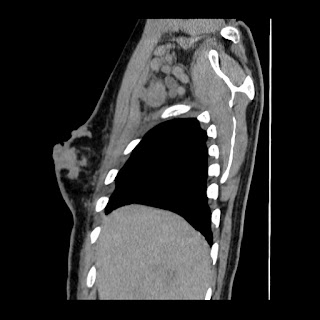

A 62 years old man with enlarged mole on chest since 2 months.

CT chest :-